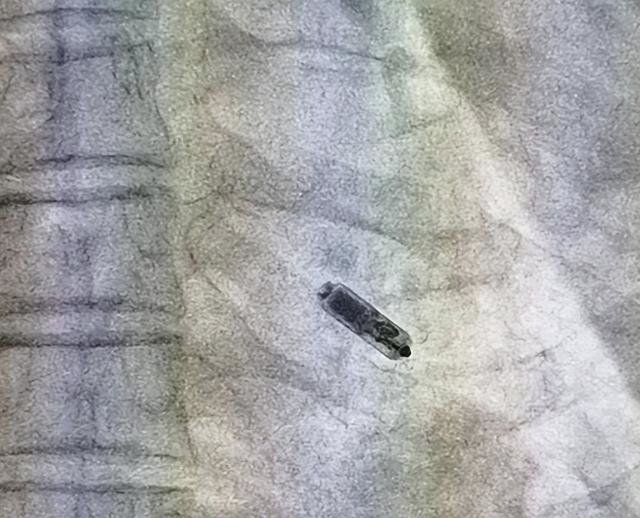

Micra,即无导线起搏器,被誉为“全球体积最小的心脏起搏器”,仅有普通胶囊大小,体积比传统起搏器减少93%,重量约2g,作为新型研发的起搏器,拥有强大的电池续航能力,同时Micra兼具抗核磁功能,可耐受1.5/3.0T核磁。手术经股静脉途径植入,无手术切开,体内血管无电极导线,避免了传统起搏器囊袋感染、电极磨损、静脉血管闭塞等风险。